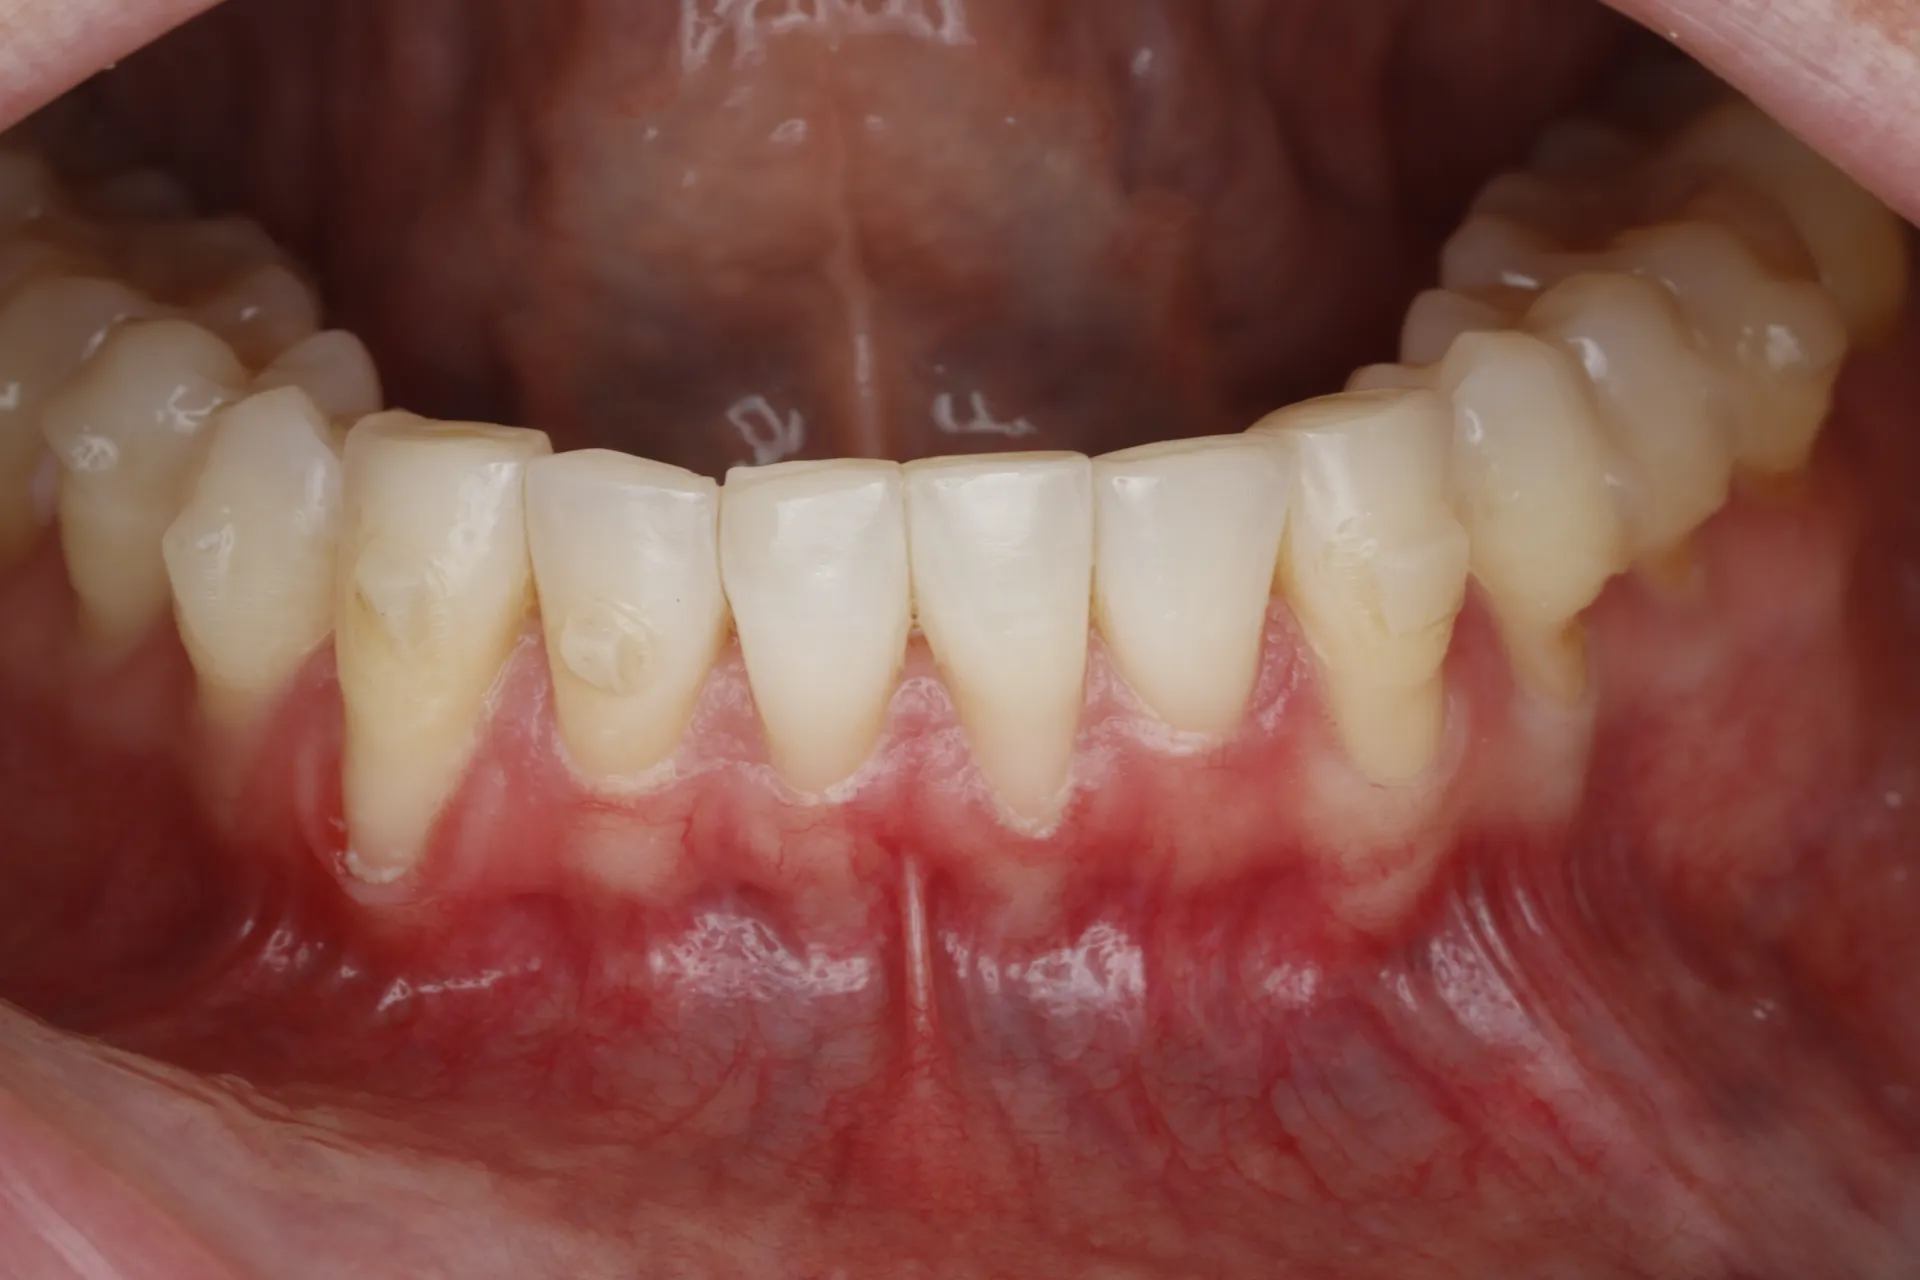

Gum Recession